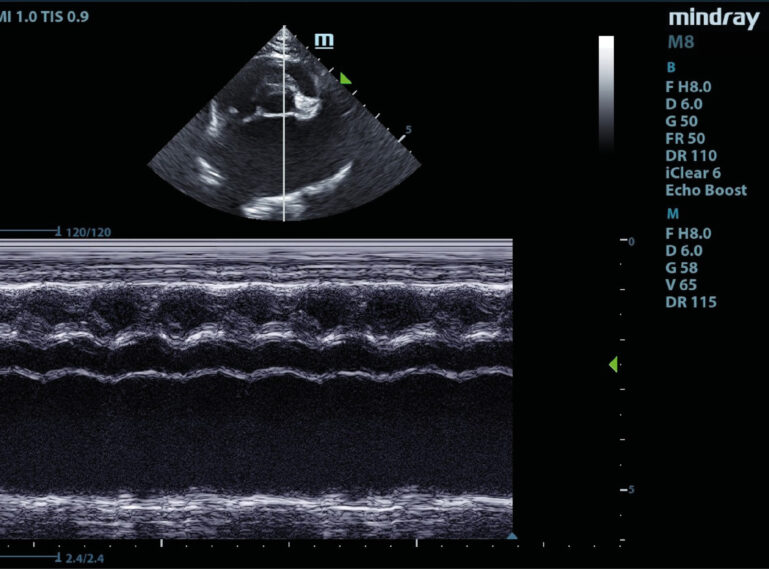

Una vez confirmado el FATE, resulta esencial realizar una evaluación completa del paciente para detectar posibles comorbilidades. El uso combinado de PoCUS (cardiac point of care ultrasound) cardiaco (CPoCUS, vídeo 3) y PoCUS torácico (TPoCUS) permite una evaluación rápida de las estructuras cardiacas y torácicas. Además, el CPoCUS puede ayudar a identificar un origen cardiogénico del evento; no obstante, no reemplaza una ecocardiografía completa realizada por un cardiólogo veterinario21.

En gatos que han padecido FATE o presentaban signos de elevado riesgo de FATE, como la presencia de trombos intracamerales (vídeo 4), smoke en la aurícula izquierda (vídeo 5), disminución de la función sistólica auricular (imagen 3) o disminución de la velocidad del flujo sanguíneo en la orejuela de la aurícula izquierda, se observó una respuesta positiva al uso conjunto de clopidogrel (18,75 mg cada 24 h por vía oral) y rivaroxabán (2,5 mg cada 24 h por vía oral) y un efecto sinérgico de ambos fármacos27,28. Sobre la base de estos hallazgos, parece lógico adoptar un enfoque de terapia dual con clopidogrel y rivaroxabán/apixabán en pacientes con FATE tras el alta hospitalaria, aunque se requiere una mayor investigación para evaluar la eficacia clínica de manera más amplia5.